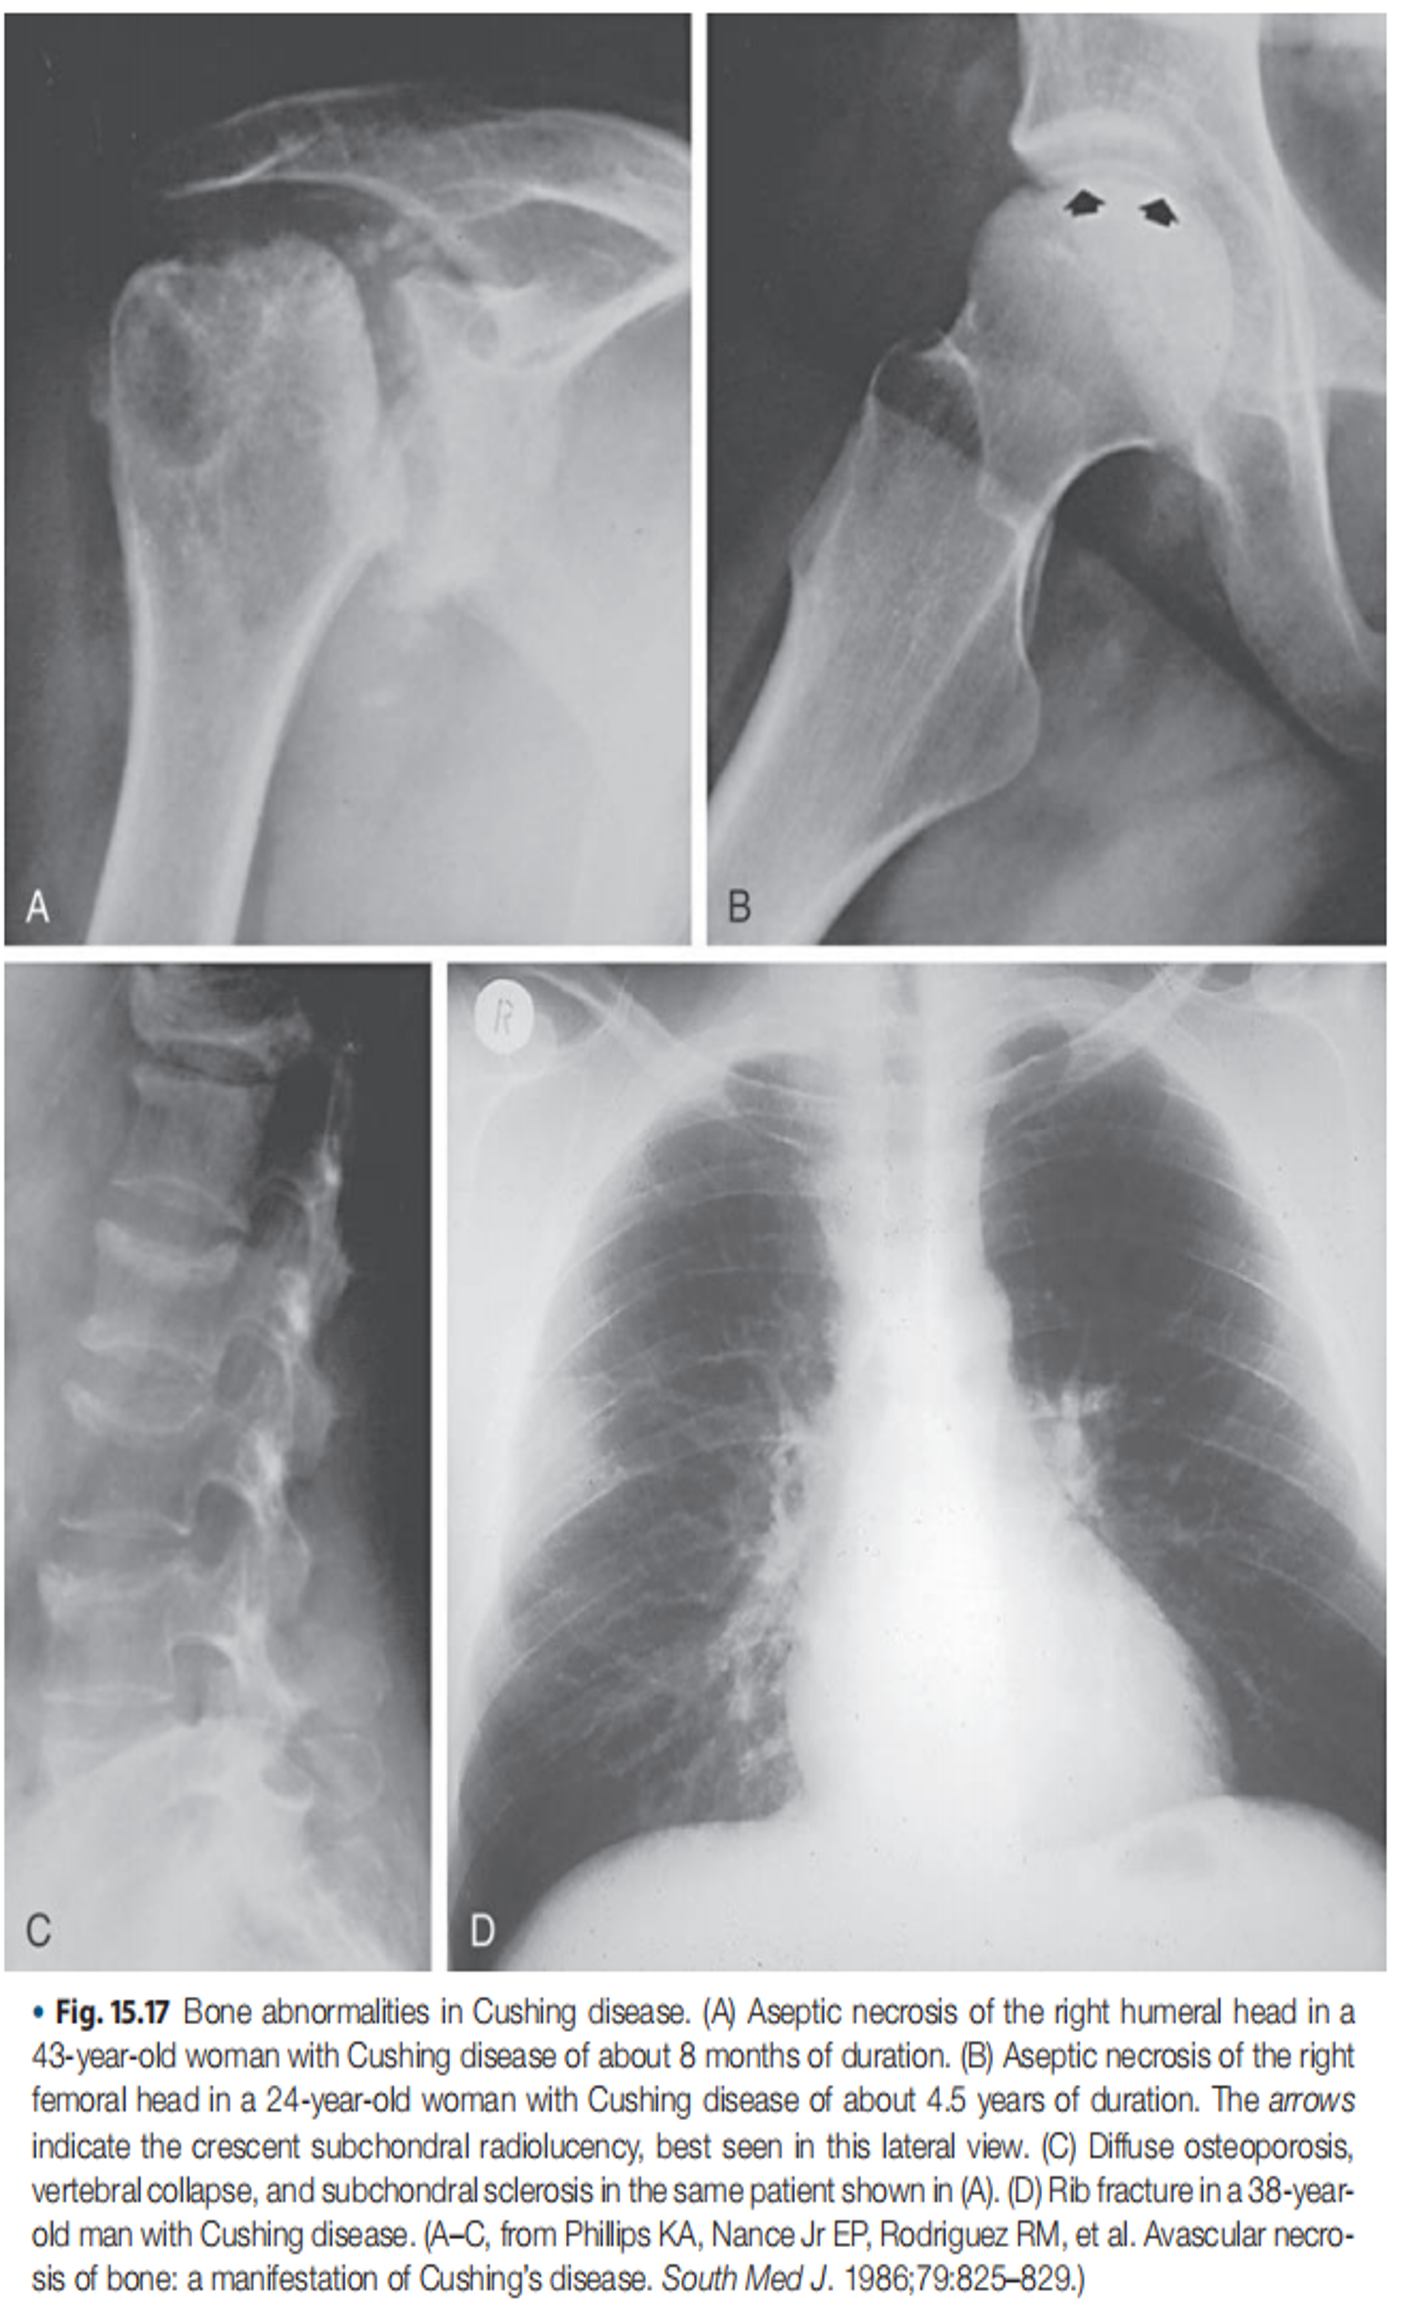

- Osteoporosis (weakened bones) in both men and women

- Inferior Petrosal Sinus Sampling (IPSS): The gold standard for differentiating pituitary from ectopic ACTH secretion.

- MRI of the Pituitary: To visualize the pituitary gland and identify potential adenomas.